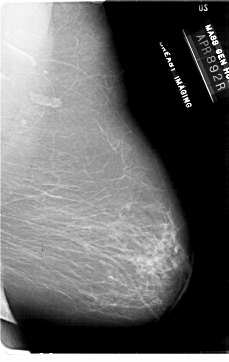

A_1862_1.LEFT_MLO

LEFT_MLO LINES 6676 PIXELS_PER_LINE 4651 BITS_PER_PIXEL 12 RESOLUTION 43.5 NON_OVERLAY